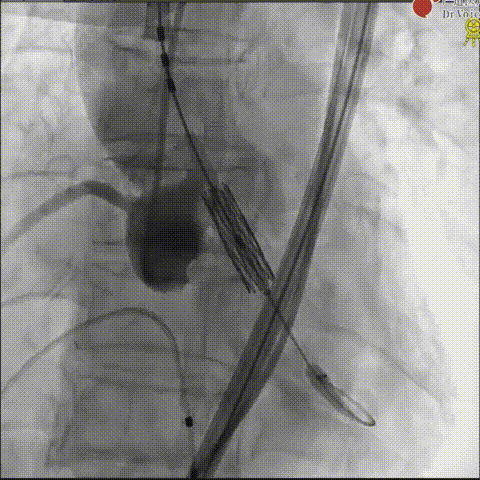

第二例患者病情更为复杂,除 Type 0 型二叶式主动脉瓣重度狭窄外,还伴有主动脉瓣明显增厚钙化、开放严重受限、心功能 NYHA II 级等问题,且患者明确拒绝外科手术,TAVR成为唯一有效治疗方案。考虑到患者钙化程度高,团队术前制定个性化方案,并决定术中应用脑保护装置,降低手术风险。

置入脑保护装置

手术过程中,团队在球囊预扩尺寸、瓣膜释放位置及后扩容积等关键环节与GISE主席团专家进行了深入探讨。

团队首先采用18mm球囊进行预扩处理,为23mm瓣膜输送开辟通路;瓣膜释放阶段,考虑到钙化团块扩张有一定不确定性,为安全起见,通过快速起搏配合减1.5cc容积“downsize”释放策略,实现瓣膜初步精准定位;释放后造影发现瓣周漏,团队随即与GISE主席团专家在线沟通,共同探讨瓣膜后扩优化方案,最终选择增加1.5cc球囊进行后扩,术后瓣周漏明显减少至微量,食道超声确认瓣膜位置、形态及功能均达理想状态,手术取得圆满成功。

球囊预扩

瓣膜释放